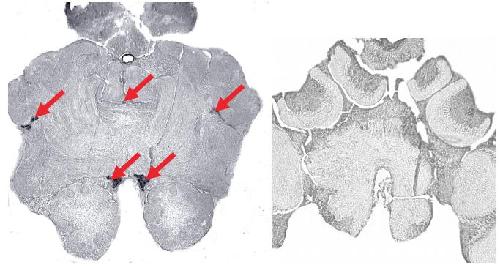

Kv3.1 channelopathy: a novel loss-of-function variant and the mechanistic basis of its clinical phenotypes., Li X, Zheng Y, Li S, Nair U, Sun C, Zhao C, Lu J, Zhang VW, Maljevic S, Petrou S, Lin J., Ann Transl Med. September 1, 2021; 9 (18): 1397. |